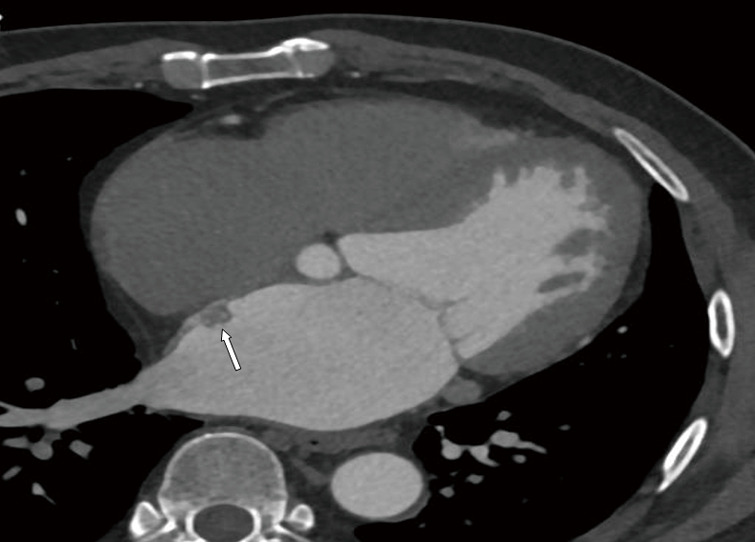

Left atrial myxoma complicated by a coronary artery fistula due to rupture of the feeding artery: a case description.

左房黏液瘤并发供血动脉破裂致冠状动脉瘘1例。